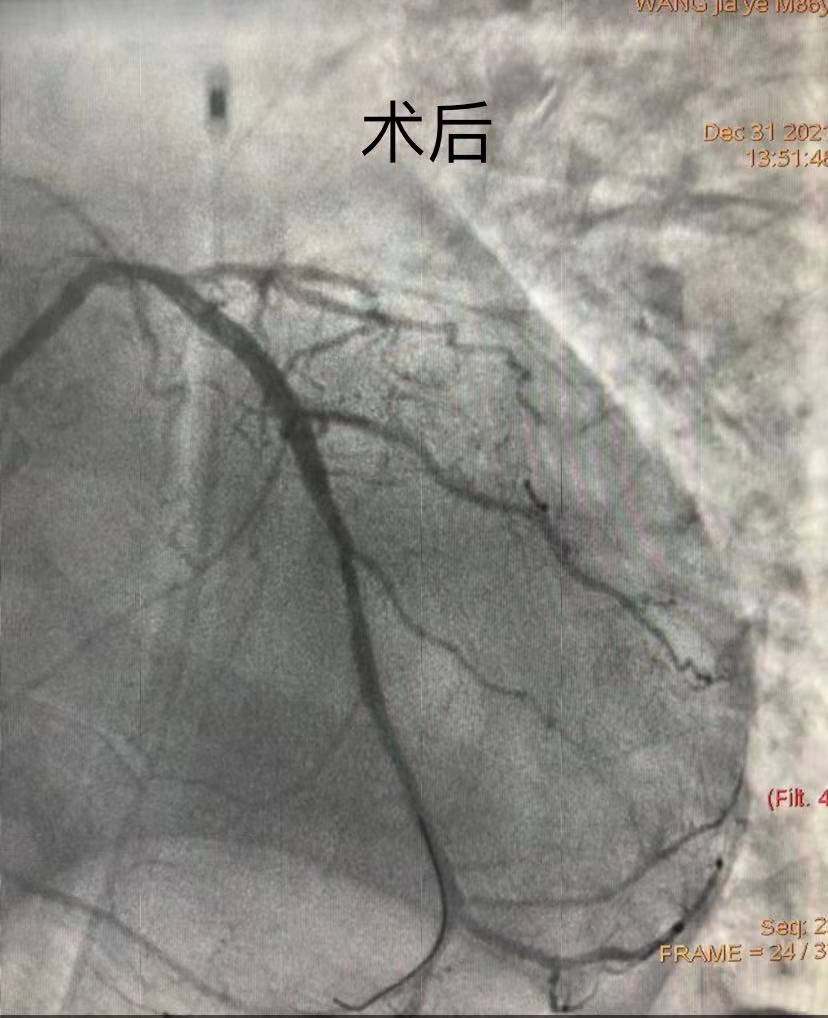

團(tuán)隊(duì)綜合考慮后判斷,LCX是此次心肌梗死的“元兇”。開通病變部位的機(jī)會(huì)只有一次,必須做到“快、準(zhǔn)、狠”。汪院長團(tuán)隊(duì)經(jīng)驗(yàn)豐富,技術(shù)嫻熟,導(dǎo)絲小心通過,球囊充分?jǐn)U張,最后在病變部位植入支架,所有操作一氣呵成。復(fù)查造影顯示,病變部位狹窄小于10%,手術(shù)獲得成功。